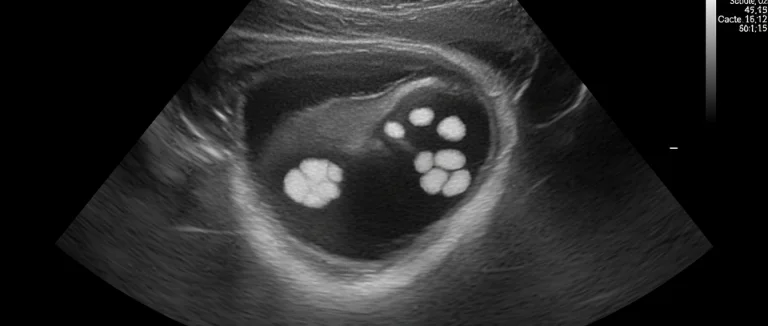

| УЗИ почек | Определить размер и локализацию камня | Размер, количество, расположение |

| КТ без контраста | Точная визуализация камней | Форма, плотность, возможный путь выхода |

| Рентгенологический скрининг (KUB) | Отслеживание движения камня | Изменение положения со временем |

Для оценки возможности естественного вывода камня используют ультразвуковое исследование (УЗИ) почек, которое показывает размер и локализацию камня, компьютерную томографию без контраста (КТ) – детальную визуализацию формы и плотности, а также рентгенологический скрининг KUB для отслеживания движения камня со временем. При подозрении на вывод через кишечник дополнительно проводят анализ кала на наличие кристаллических частиц.